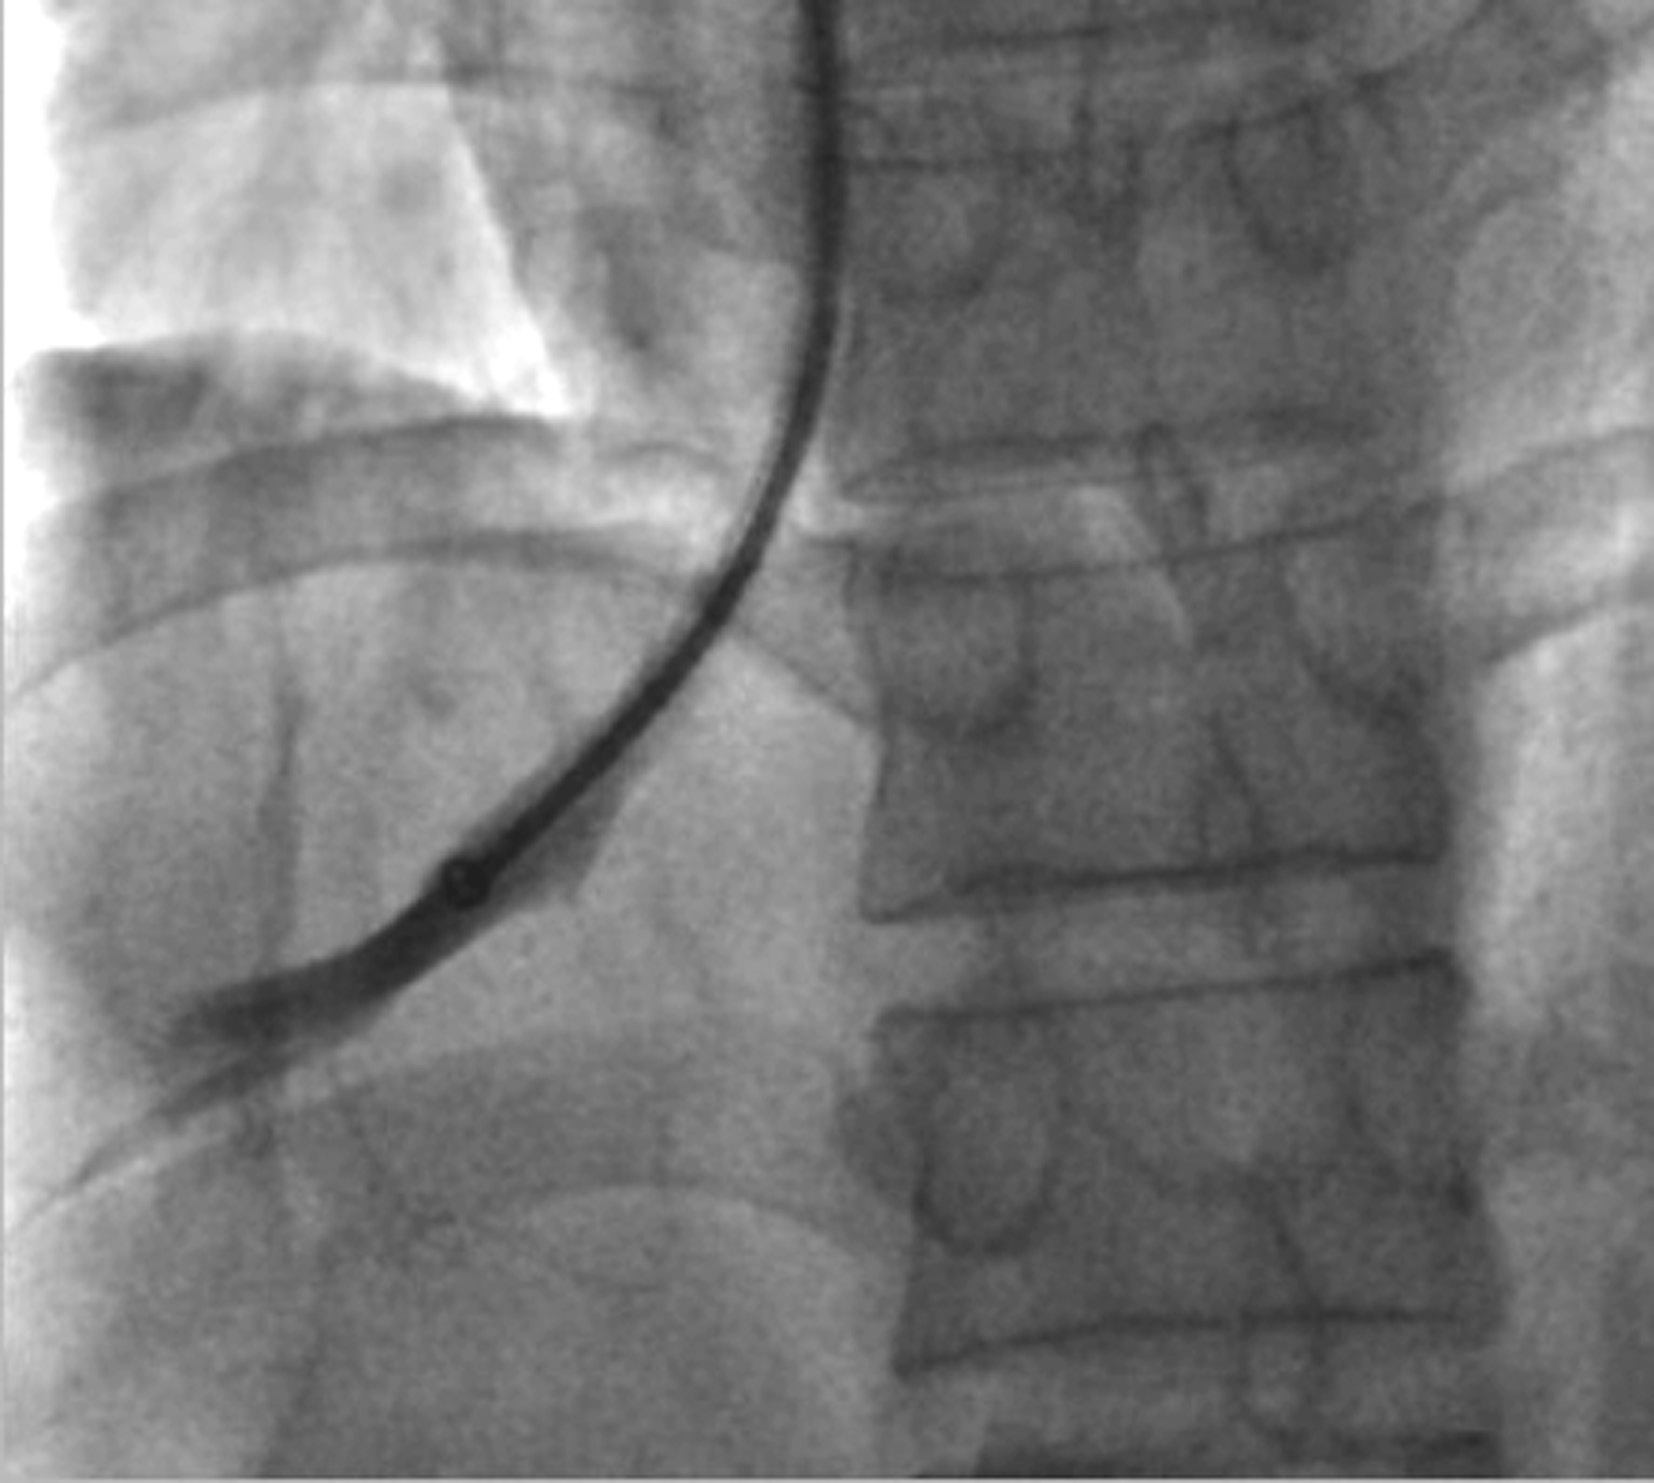

TJLB需要有经验的介入医生进行操作,患者仰卧于DSA检查床,常规予心电、血压及血氧饱和度监测。头左偏暴露右侧颈静脉区域,常规消毒、铺巾;2%利多卡因5mL局部麻醉后,采用Seldinger技术穿刺右侧颈内静脉,引入9F导管鞘(头端预成形为弯形),导管导丝配合将导管鞘经右心房进入下腔静脉;首先行下腔静脉DSA确认无明显下腔静脉狭窄,再将导管鞘进入肝静脉(常规选择肝右或肝中静脉),再造影确认肝静脉无明显狭窄闭塞(图5-22-1),其间分别检测右房、下腔静脉及肝静脉压力;将导管鞘头端进一步深入肝右静脉远端、距离下腔静脉3~4cm处,经鞘引入7F肝穿活检针;确认位置后嘱患者屏住呼吸,旋转导管鞘头端指向正下方,开启活检枪完成肝实质活检(图5-22-2);退出活检针,视获得肝组织大小决定是否再次获取肝组织,最后行肝静脉造影排除明显异常。术后患者平卧并监测心电、血压、血氧饱和度4h,术后24h 复查血常规、凝血功能等指标。

图5-22-1 肝静脉造影